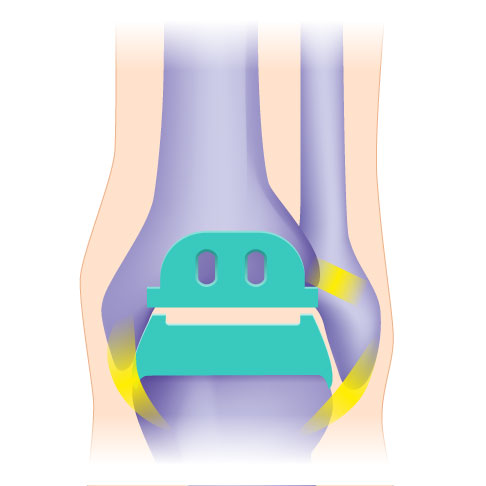

Individualisierte TEP (Totalendoprothese) mit 3 Komponenten:

- gerundete Kappe für die Sprungbeinrolle

- Platte für die Schienbeingelenkfläche

- frei beweglicher Polyethylen-Gleitkern

Die Drei-Komponenten-Prothese ist im Vergleich zur Zwei-Komponenten-Prothese flexibler. Sie unterstützt die natürliche Biomechanik des Sprunggelenks, weil sie in alle Richtungen beweglich sind. Die Drei-Komponenten-Prothese kann bei stabilen und korrekten Achsverhältnissen knochensparend eingesetzt werden.

Bei den individualisierten TEP (Totalendoprothesen) für das Sprunggelenk werden sowohl das Sprungbein (Talus) als auch die Schienbeingelenkfläche (Tibiagelenkfläche) mit einer Metallkappe überzogen. Die Rückflächen der Kappen sind titanbestrahlt und mit Hydroxylapatit beschichtet und gehen während des Heilungsprozesses eine stabilen Verbindung mit dem natürliche Knochen ein.

Die dritte Komponente der Prothese ist ein frei beweglicher Polyethylen-Gleitkern, der die wichtige Bewegung zwischen den beiden Gelenkpartnern vermittelt. Die freie Beweglichkeit des Gleitkernes ermöglicht eine uneingeschränkte Belastung der Prothesenflächen. Die Kunststoffkerne wurden in den letzten Jahren optimiert. Sie sind härter und bewirken eine bessere Quervernetzung des Polyethylens.